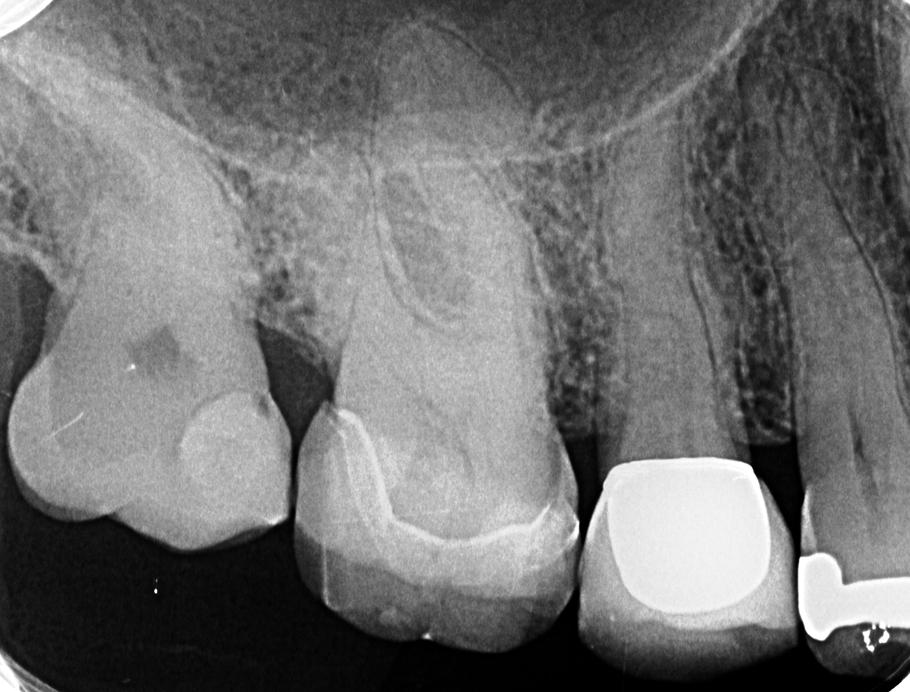

01 Ausgangsaufnahme

910 × 692

Durchblick